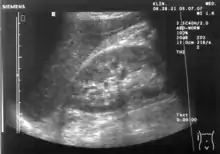

A normal ultrasonographic view of Morison's pouch. The bright line is the capsule of the kidney; there is no fluid present and hence no visible space.

Ultrasound of liver (left side of the image) and right kidney (right side of the image) and Morison's pouch, not containing fluid